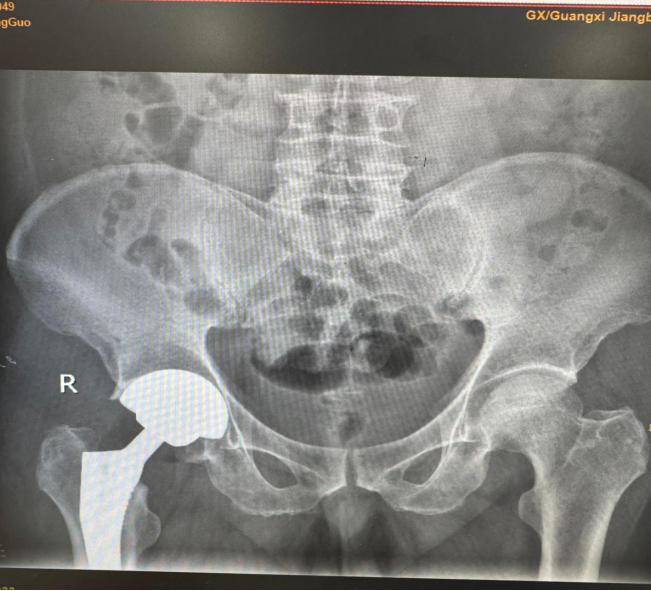

2、关节专科:关节内骨折,脱位复位内固定术;半月板损伤,关节韧带损伤行关节镜微创修复及关节功能重建术;膝关节表面置换术,人工股骨头置换术,全髋关节置换术,假体周围骨折重建及返修术,股骨头缺血坏死血管介入治疗,钻孔减压及异体骨植入术,带血管肌骨瓣植入术等。

髋关节置换术